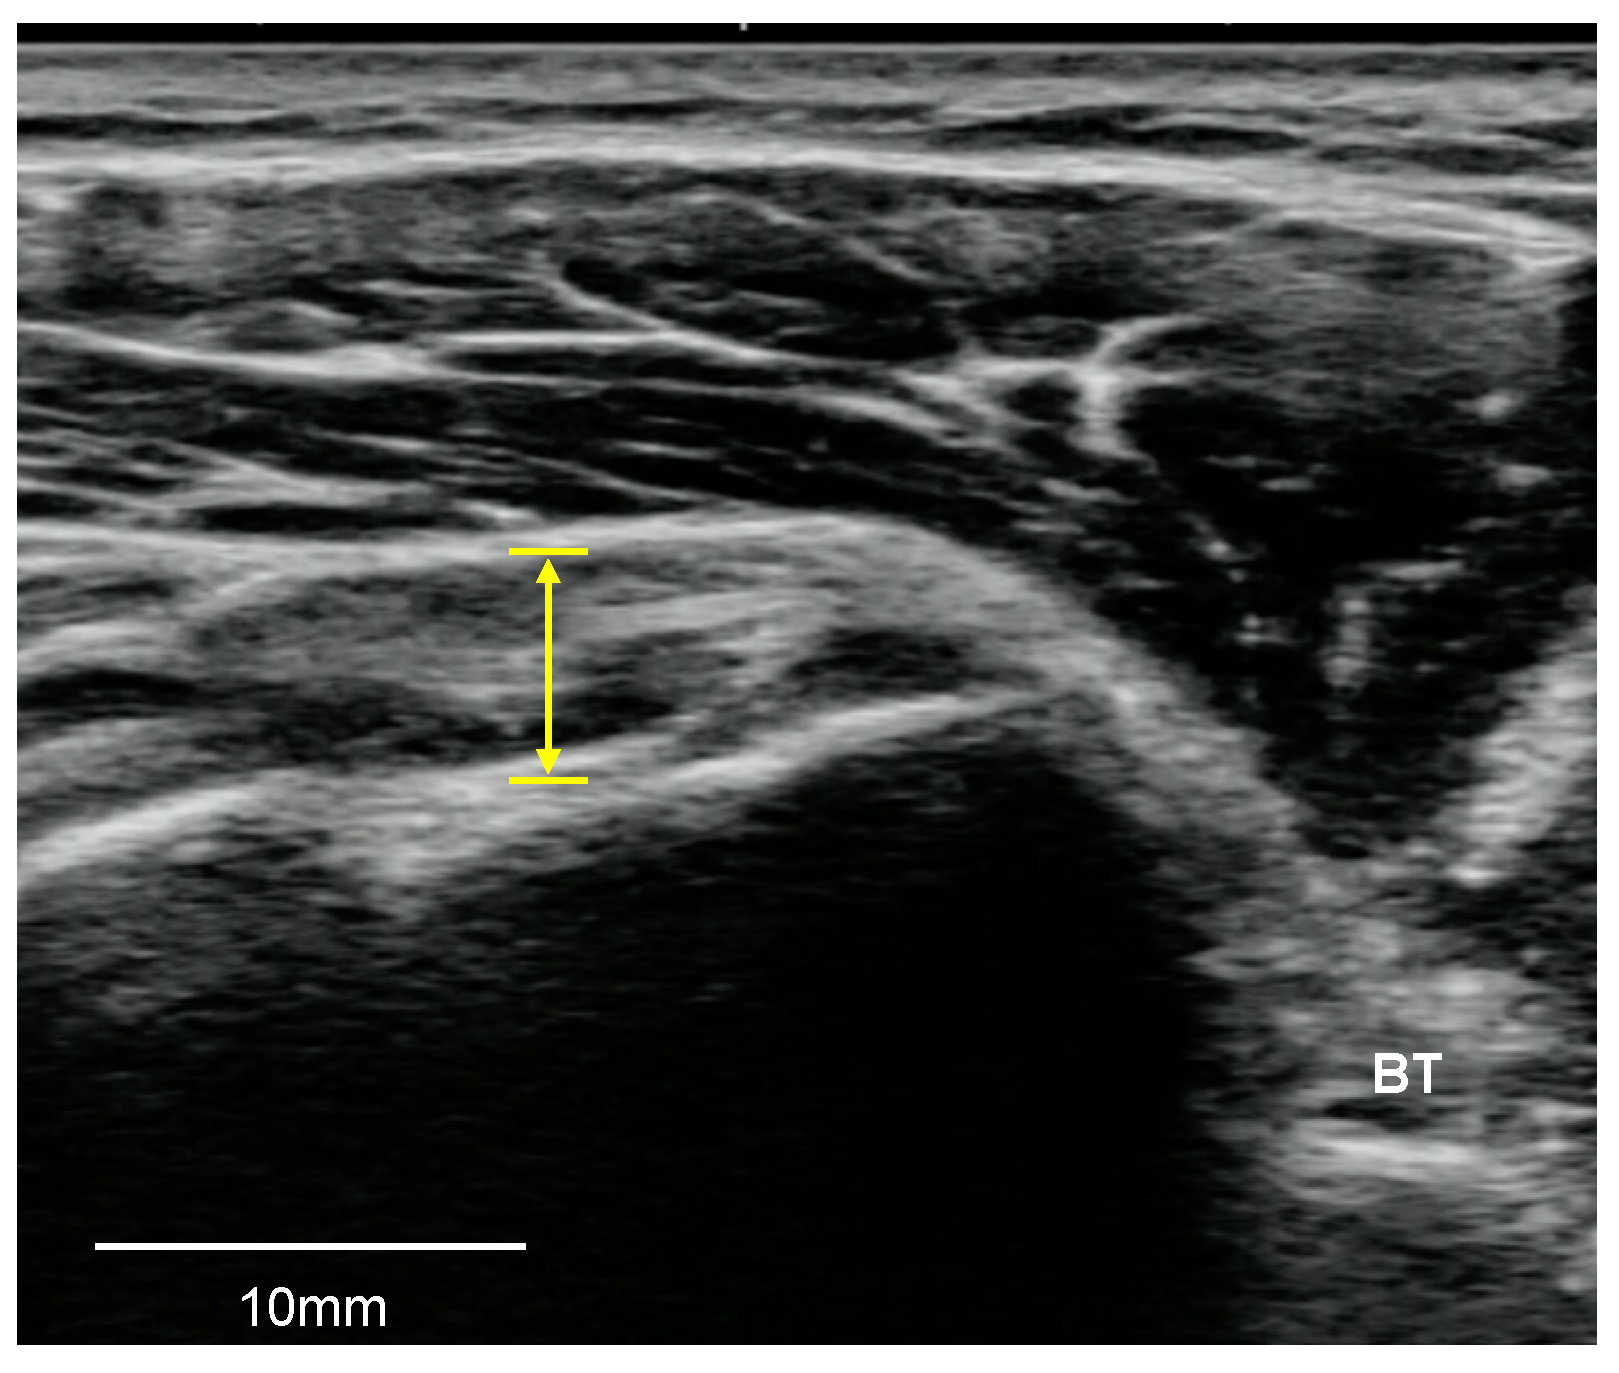

2.3.1. LHB Tendon

2.4. Statistical Analysis